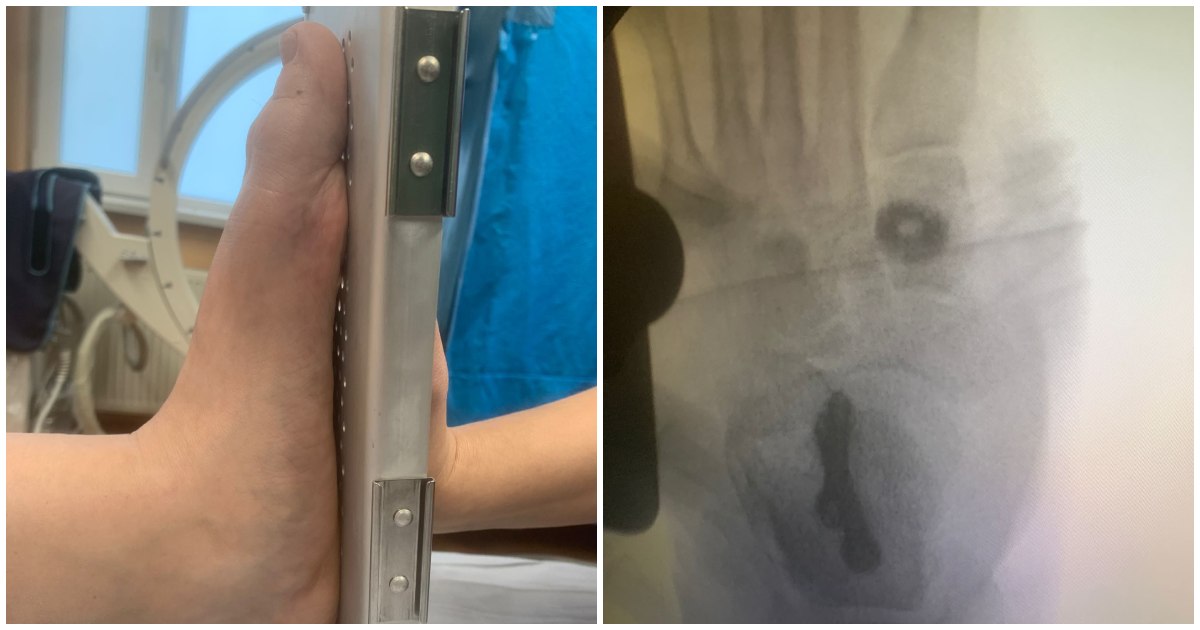

"Astăzi, la Spitalul Județean Satu Mare, echipa condusă de medicul Răzvan Anițaş a realizat prima intervenție din România cu un implant Osteosinter de la Ames Medical pentru o pacientă de 56 de ani cu platfus (pes planus) de gradul IIB.", informeză cei de la RONDA Medical.

Potrivit sursei citate, procedura inovatoare, care include osteotomie calcaneală cu deplasare medializată -MDCO (medializing displacement calcaneal osteotomy) urmată de osteotomia Cotton, oferă o soluție modernă și eficientă pentru pacienții cu picior plat în diverse stadii de evoluție.

"Prin utilizarea implanturilor Osteosinter Cotton & Evans, tratăm aceste afecțiuni ca oriunde altundeva in Europa. Mulțumim medicului Răzvan Anițaş pentru deschiderea unei noi căi de tratament, facilitând accesul la terapii moderne pentru pacienți", au mai precizat cei de la RONDA Medical.